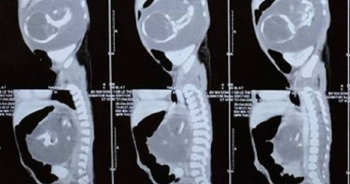

Bé trai chào đời mang theo người em song sinh… trong bụng

Chào đời với khối u có kích thước lớn trong bụng, bác sĩ xác định đó chính là người em song sinh của bệnh nhi.